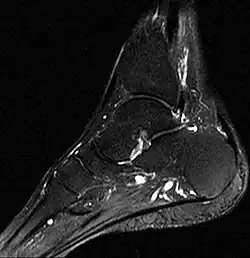

- Fuß, MRT, T2-Gewichtung

-

Zum Vergleich: Sprungbein, Kahnbein und Keilbein unauffällig